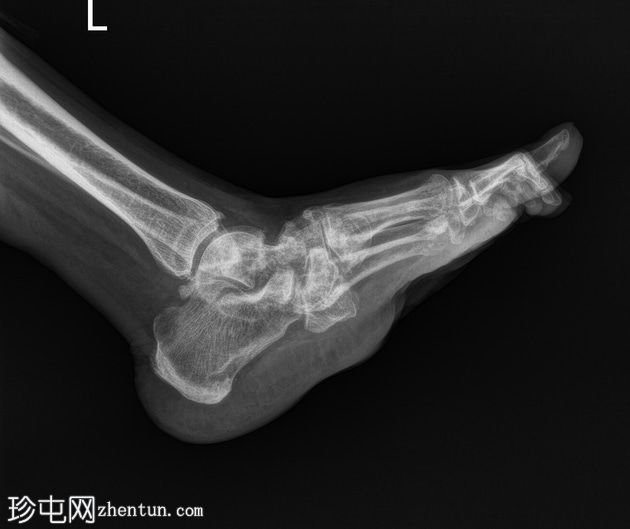

侧位片

双足均符合典型的夏科氏关节病特征,该患者为已知糖尿病患者。

该病表现为骨质疏松、骨硬化(密度改变)、跗骨碎裂和破坏、关节内游离体(碎屑)、软组织肿胀和关节积液(扩张)、中足结构紊乱以及跗跖关节错位(脱位)。

X线平片未见气性坏疽或化脓性关节炎的证据。